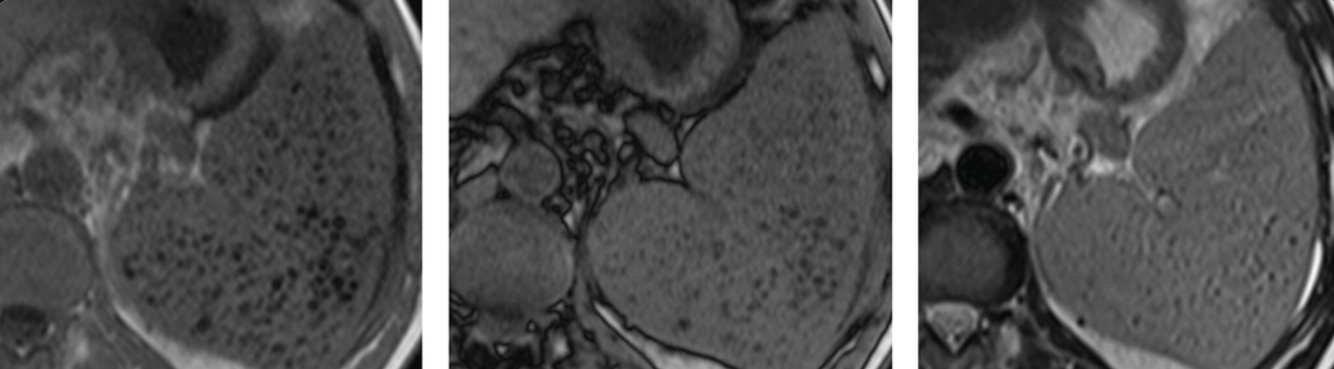

68yo female; Dx?

Dx: pancreatic serous cystadenoma.